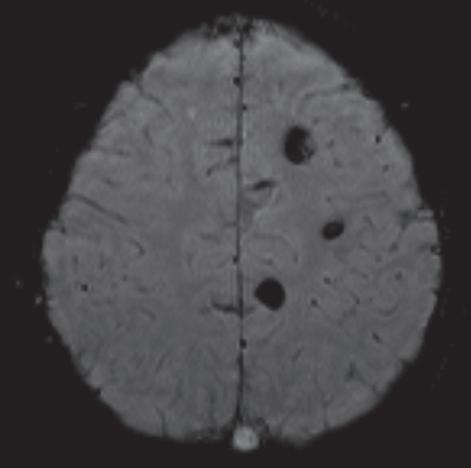

La exploración fue realizada con resonador magnético de alto campo, (1.5 Tesla), Siemens SPREE en cortes axiales, sagitales y coronales, en secuencias ponderadas en T1, T2, FLAIR, Difusión (DW), susceptibilidad (SWI) con la administración de contraste endovenoso paramagnético, fase angiográfica y espectroscopía.

En el lóbulo frontal derecho, se observa un hematoma en el parénquima, sus dimensiones 4,5 cm x 3,6 cm x 3,1 cm, de comportamiento hiperintenso en T1, T2 y FLAIR, de paredes gruesas hipointensas en las secuencias GRE, con restricción hídrica central en difusión y leve edema periférico, condicionando borramiento de los surcos corticales. También condiciona laminación del ventrículo lateral derecho. (Fig.1)

Secuencia de SWI 3D evidencia múltiples imágenes hipointensas, de formas nodulares, algunas de ellas presentan contornos lobulados, distribuidas en ambos hemisferios cerebrales, sin edema

periférico. Sus diámetros oscilan entre 0,2 y 0,8 cm. (Fig. 2,3,4,). Con el medio de contraste no hay cambios en la intensidad de señal.

En las imágenes evaluadas en T2 y FLAIR es posible observar un foco hipointenso en el lóbulo frontal y otro a nivel del lóbulo temporal izquierdo, las demás lesiones son imperceptibles. En la evaluación de espectroscopía con multivoxel a nivel de la lesión frontal derecha se aprecia disminución de NAA, sin variación importante de Cho y Cr, incremento considerable de lactato, hallazgo en relación a lesión vascular aguda. (Fig.5)

Cavernomas múltiples complicados con hematoma intraparenquimatoso frontal derecho, secundario a cavernoma accidentado.